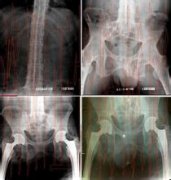

QZ16030094 姓名:陈先生 性别:男 年龄:32岁

- 病情

AS ①晚期 ②重度 病史:5年+

- 治疗

治疗后骶髂关节疼痛消失,腰椎前屈、背伸侧弯活动自如,膝关节无压痛感,复查血沉、C反应蛋白、等各项检查均已达到临床康复的标准。